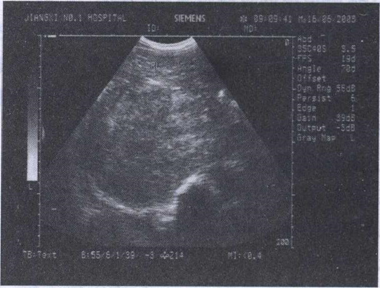

49.男,50岁,右上腹疼痛,乏力,食欲缺乏。结合超声声像图,诊断为()